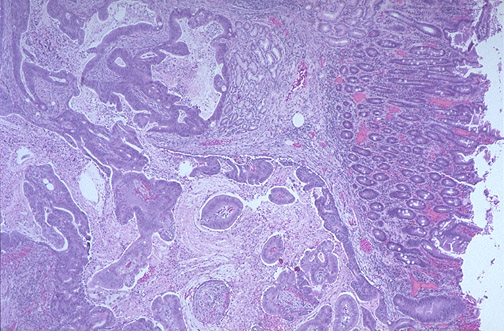

| This adenocarcinoma arose in the ampulla of Vater. Primary small intestinal carcinomas are very rare, but the majority of those that do occur arise in the region of the ampulla, where they may become symptomatic through biliary or pancreatic duct obstruction. The appearance of such a mass on esophagogastroduodenoscopy is seen below, and following placement of a stent for drainage. |